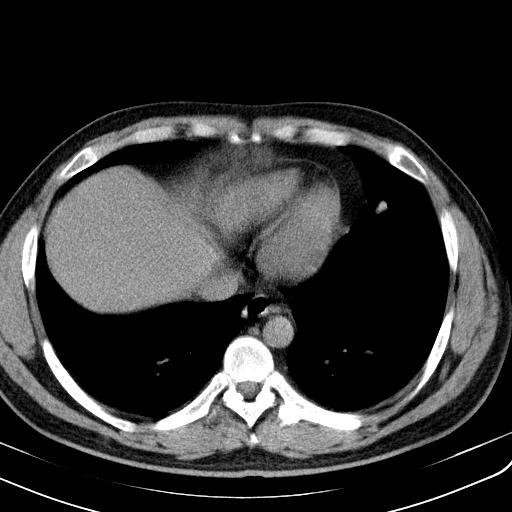

患者男性 35 主因发热咳嗽四天,血象不高,心肺听诊未见异常,无其它病史及传染病接触史。

一周后复查胸片基本正常

两肺散在大小不等小结节影,下野较多,纵隔淋巴结增大。考虑:1、慢性血播性肺结核;2、霉菌病?3转移瘤待排。

该病人肺内多发结节,右肺门似有肿大淋巴结,肺结节病也要考虑

肺内纵隔多发结节,肺内以外周为著,首先考虑转移瘤

两肺多发结节,部分病灶边缘不清,且示毛玻璃影。分布特点为沿血管支气管分布。

结合临床考虑;1,炎性肉芽肿性病变;霉菌?过敏性肺炎?2,韦格氏肉芽肿。3,转移瘤。

补充一下各种检查结果,病人无痰,胸闷,ppd及结核抗体阴性,wbc7.5x10的9次方,血沉22mm/h,crp及抗链o阳性。

经一周抗炎抗病毒治疗复查胸片示病变大部吸收,基本恢复正常,未做气管镜检查,考虑为炎性变或霉菌感染。